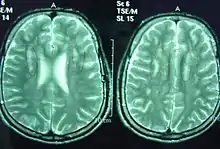

Diagnosis

Diagnosis is made with a blood test which sees if the activity of the fatty aldehyde dehydrogenase enzyme is normal.[4] Gene sequencing can also be used, which can additionally be used by would-be parents to see if they are carriers.[4]